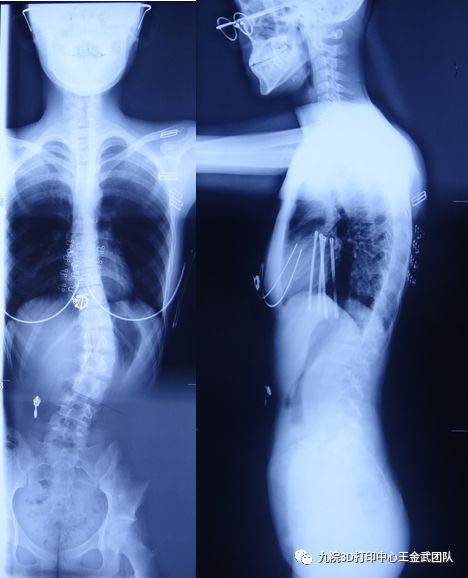

初诊:2018年8月,患者女,14岁余,于2年前发现脊柱侧弯,未及时予以重视。自述脊柱侧弯症状逐渐加重,至当地医院就诊。脊柱全长X光片显示脊柱侧弯Cobb角35°,椎体形态、骨质尚可,部分椎体旋转。遂至我院3D打印中心门诊就诊。

患者Risser征4级,月经初潮13岁,既往月经规律;双下肢等长,骨盆稍有倾斜,躯干相对骨盆向左侧严重偏离。L2椎体楔形变,椎体旋转3级,剃刀背,骨性偏硬。颈椎曲度变直,胸椎和腰椎生理曲度尚可。